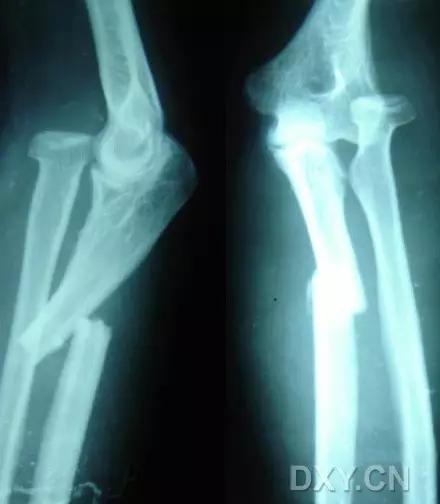

9. Monteggia 骨折(孟氏骨折)

尺骨近端 1/3 骨折合并桡骨头半脱位。

成人 Monteggia 骨折

儿童 Monteggia 骨折